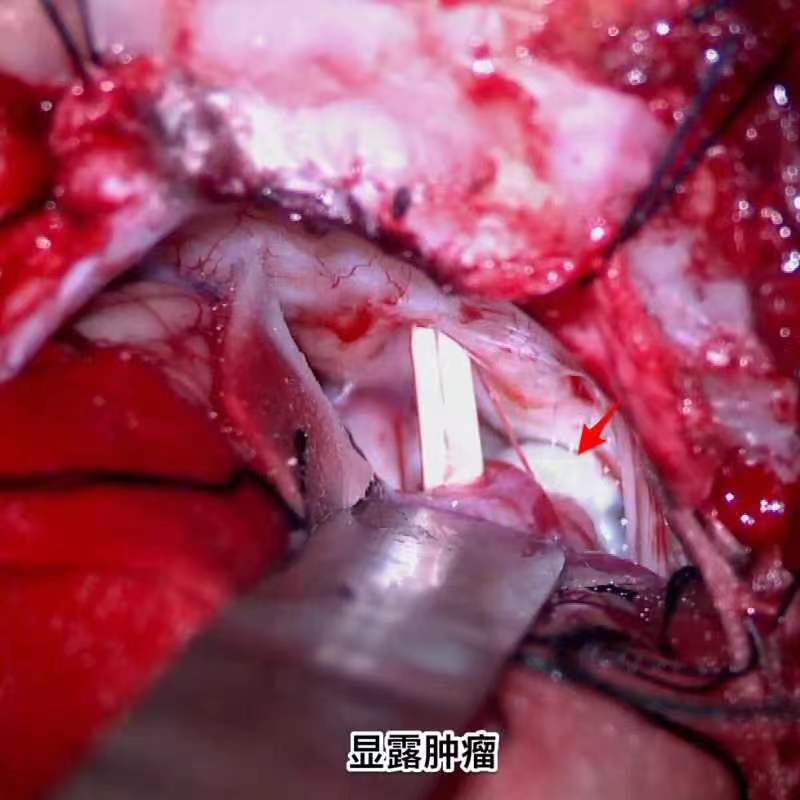

昆明三博2023:表皮样囊肿切除术

脑肿瘤-皮样囊肿/表皮样囊肿